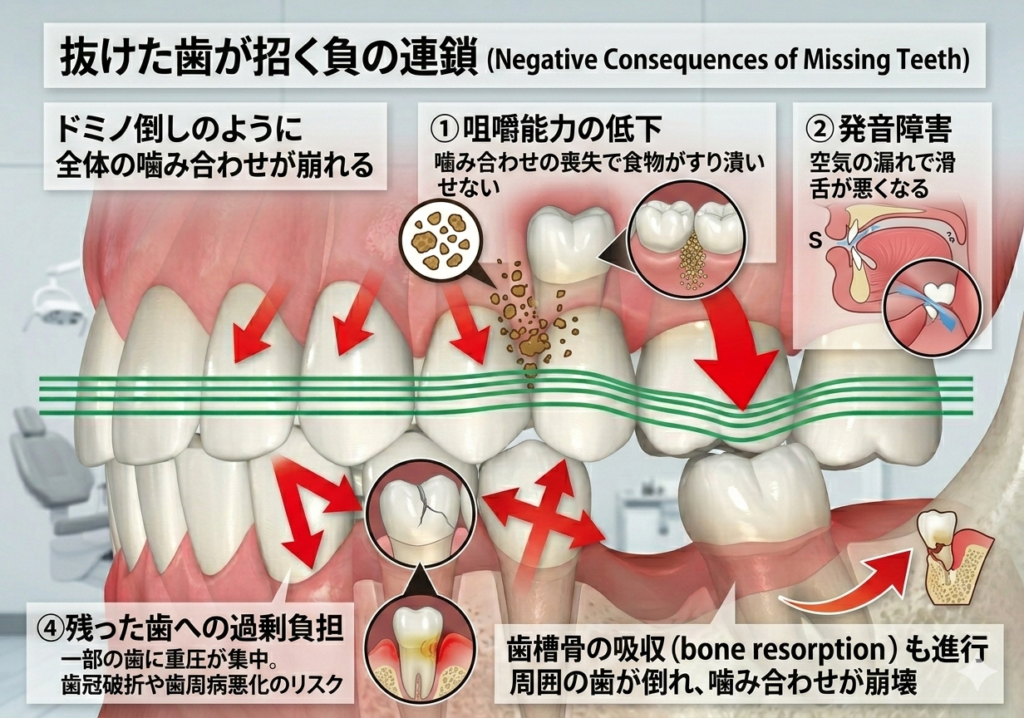

抜歯後、歯を放置すると起こる事

①咀嚼能力の低下で噛みにくくなる

②発音障害で喋りにくくなる

③歯が無いところに隣の歯が傾き、歯並び、噛み合わせが悪くなる

④残った歯に過剰な力がかかり、歯が折れたり、歯周病が加速したりする可能性が高まる

特に③④を放置すると、残った健康な歯に負担がかかったり、さらなる歯の喪失につながる危険性があります。できるだけご自身の歯を長持ちさせたい方は特に放置はせずに治療を検討されることをオススメします。